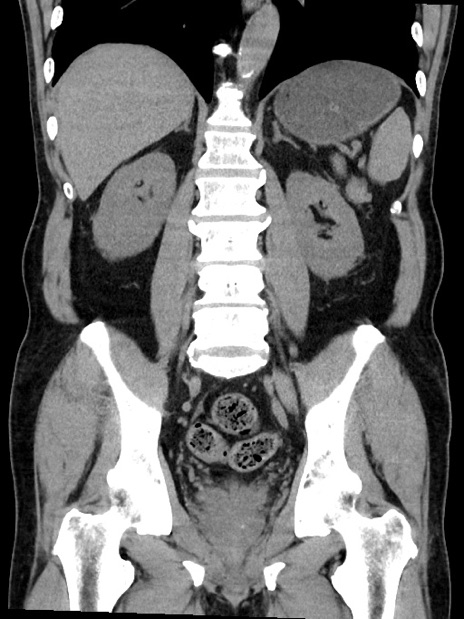

症例35(冠状断像)

【症例】70歳代 男性

【主訴】腹部膨満、嘔吐

【現病歴】昨日より腹部膨満感出現。本日増悪し、仙痛出現。嘔吐あり、受診。

【既往歴】糖尿病、胆摘後

【身体所見】BP 149/80mmHg、HR 74/min、BT 35.9℃、腹部:膨満、軟、圧痛なし。腸雑音減弱あり。上腹部正中切開瘢痕あり。

【データ】WBC 13500、CRP 1.72